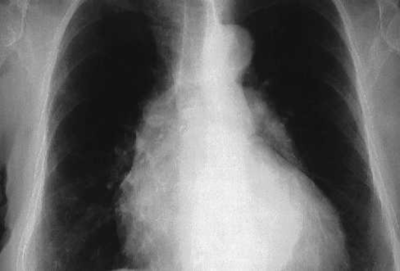

Mujer de 46 años sin antecedentes patológicos relevantes. No tiene alergia a medicamentos. Fumadora de 10 cigarros por día. Desde una semana antes de su ingreso comienza con fiebre de hasta 38º C y dolor torácico retroesternal de carácter punzante, que aumenta con la tos pero no con los movimientos y que cede con ibuprofeno. No expectoración. Pruebas complementarias: ECG: ritmo sinusal a 100 lats/min Hemograma: Leucocitos 15.39 10E3/µL, (N 89.3 %, L 4.4 %, M 4.5 %, Eo 0.7 %, B 0.2 %), Hb 11.4 g/dL, Hcto. 33.1 %, VCM 77.8 fL, Plaquetas 428 10E3/µL. Coagulación y bioquímica sin alteraciones relevantes. CPK y troponina Ic normales. La radiografía de tórax de la paciente se muestra en la figura 1. En ella lo más llamativo es la presencia de una discreta cardiomegalia. Se presenta radiografía. ¿Cuál es su diagnóstico?

Answer

• Derrame pericárdico, es la presencia de líquido en la cavidad pericárdica o derrame pericárdico apreciandose una imagen del corazón en forma de "botella“ en la Rx.

• Tamponamiento Cardíaco como como consecuencia de la acumulación de líquido a tensión, lo que anula el efecto de la presión negativa intratorácica sobre el llenado cardíaco y ofrece una resistencia a la expansión ventricular durante el llenado diastólico.

• Pericarditis aguda idiopática, en la segunda radiografía aplicada se aprecia además de la cardiomegalia datos sugerentes de derrame pleural bilateral.